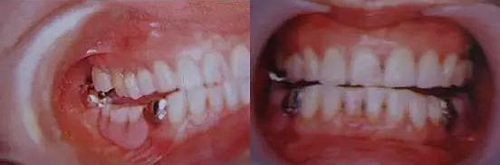

圖9. 上頜和下頜第二磨牙中發(fā)生的前方誘導(dǎo)干擾引發(fā)的張口困難。

下頜磨牙的遠(yuǎn)中頰側(cè)牙尖的近中頰側(cè)斜面和上頜磨牙的近中頰側(cè)牙尖的遠(yuǎn)中腭側(cè)斜面相接觸。

圖10. 不考慮下頜第三磨牙的咬合平面破壞的修復(fù)體制作完成后,

后方磨牙干擾引發(fā)的前方誘導(dǎo)干擾。